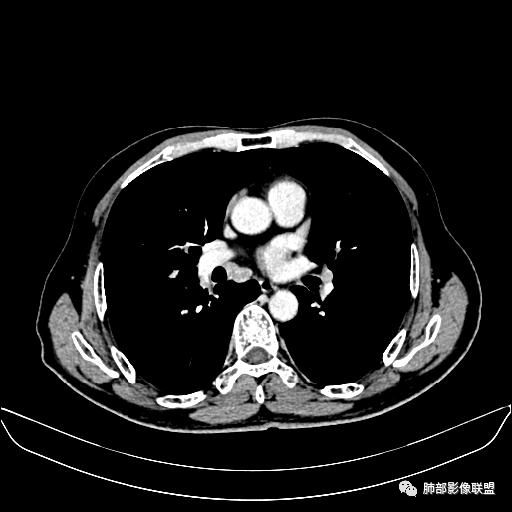

住院4天后行胸部增强CT

动脉期

老年男性,因“咳嗽咳痰1月余。”入院。病程中咳嗽咳痰,咳黄白痰,间断咯少许鲜红色痰血。PPD阳性。胸CT:右肺中叶外侧段支气管管腔阻塞,大片实性病变,病灶边缘光滑,部分边缘膨隆,可见分叶,肺门及纵隔可见肿大淋巴结,并可见钙化。增强可见病灶明显强化,而且延迟强化明显,病灶内多发低密度区,内见血管影,血管变细、部分血管破坏。考虑恶性病变可能性大,鉴别慢性肉芽肿性病变。

胸CT:跨叶大肿块,主体在中叶,右中叶外侧段支气管阻塞,病灶部分边缘膨隆,可见分叶,部分边缘平直,肺门及纵隔可见肿大淋巴结。增强病灶不均匀强化,延迟强化明显,病灶内多发低密度区,内见血管飘浮,部分血管变细、模糊。考虑:恶性病变可能性大,大细胞?淋巴瘤?鉴别慢性肉芽肿性病变。

右肺中叶软组织肿块,外围向内生长,叶间胸膜向前内移位,肿块近肺门侧跨叶,中叶外侧段支气管截断,密度不均匀,双侧肺门及隆突下见肿大淋巴结,增强后呈中度不均质强化,肺动脉供血,多发坏死区,边界尚清,坏死区域内见结构,结合病史考虑恶性,鉴别诊断1结核,爬行征是沿支气管树分布,外宽,内窄,周围有卫星灶,内气管狭窄后扩张,此例沿叶间胸膜长轴分布,气管有截断,不典型。2炎性肉芽肿,符合的地方下方层面增强后延迟性轻度环形强化,不符临床无发热等急性感染病史,实验室指标不符,病灶周围渗出及慢性炎性改变有,不明显。